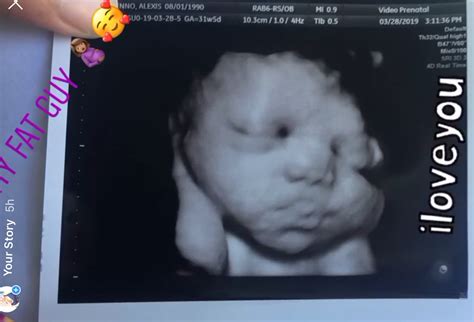

Pregnancy is a journey filled with excitement, anticipation, and a multitude of milestones. One of the most significant milestones is the 36 weeks pregnant sonogram. This ultrasound scan is crucial for assessing the baby's development and ensuring both the mother and the baby are healthy and ready for the upcoming delivery. Let's delve into the details of what to expect during this important stage.

A 36 weeks pregnant sonogram is typically performed to evaluate the baby's growth, position, and overall health. At this stage, the baby is almost fully developed, and the ultrasound can provide valuable information about the baby's readiness for birth. The sonogram at 36 weeks is often more detailed than earlier scans, offering a clearer picture of the baby's anatomy and any potential issues that may need to be addressed before delivery.

During the 36 weeks pregnant sonogram, the ultrasound technician will use a transducer to send sound waves through the abdomen. These sound waves create images of the baby on a screen. The technician will measure various aspects of the baby, including:

• Head circumference

• Abdominal circumference

• Femur length

• Estimated fetal weight

The technician will also check the baby's position in the uterus, which is crucial for planning the delivery. If the baby is in a breech position (feet or buttocks down), the healthcare provider may discuss options for turning the baby or planning a cesarean section.